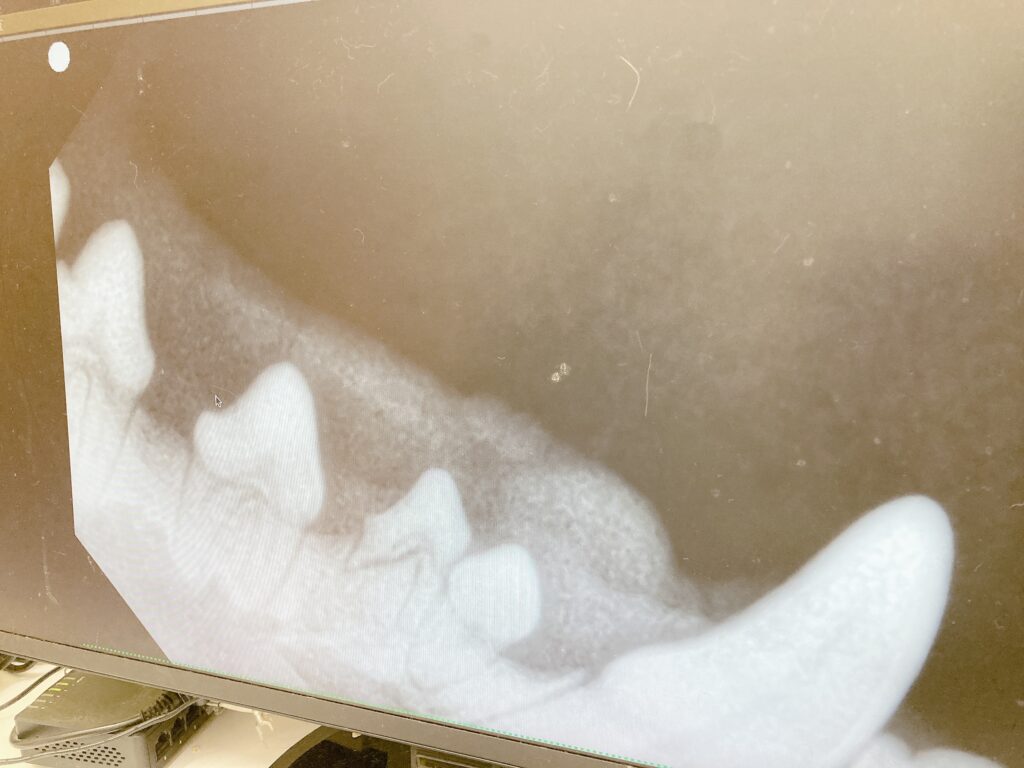

お世話になっている動物病院に歯科用のレントゲンも導入されているので

歯のレントゲンも撮って貰ってます。

レントゲンと撮って発覚したのですが、乳歯の残りなのか折れている歯が1本ありました。

幸い今まで痛みは無かった様ですが、いつ折れたのかは不明です。

歯石取りと同時に折れている乳歯を抜歯して貰いました。